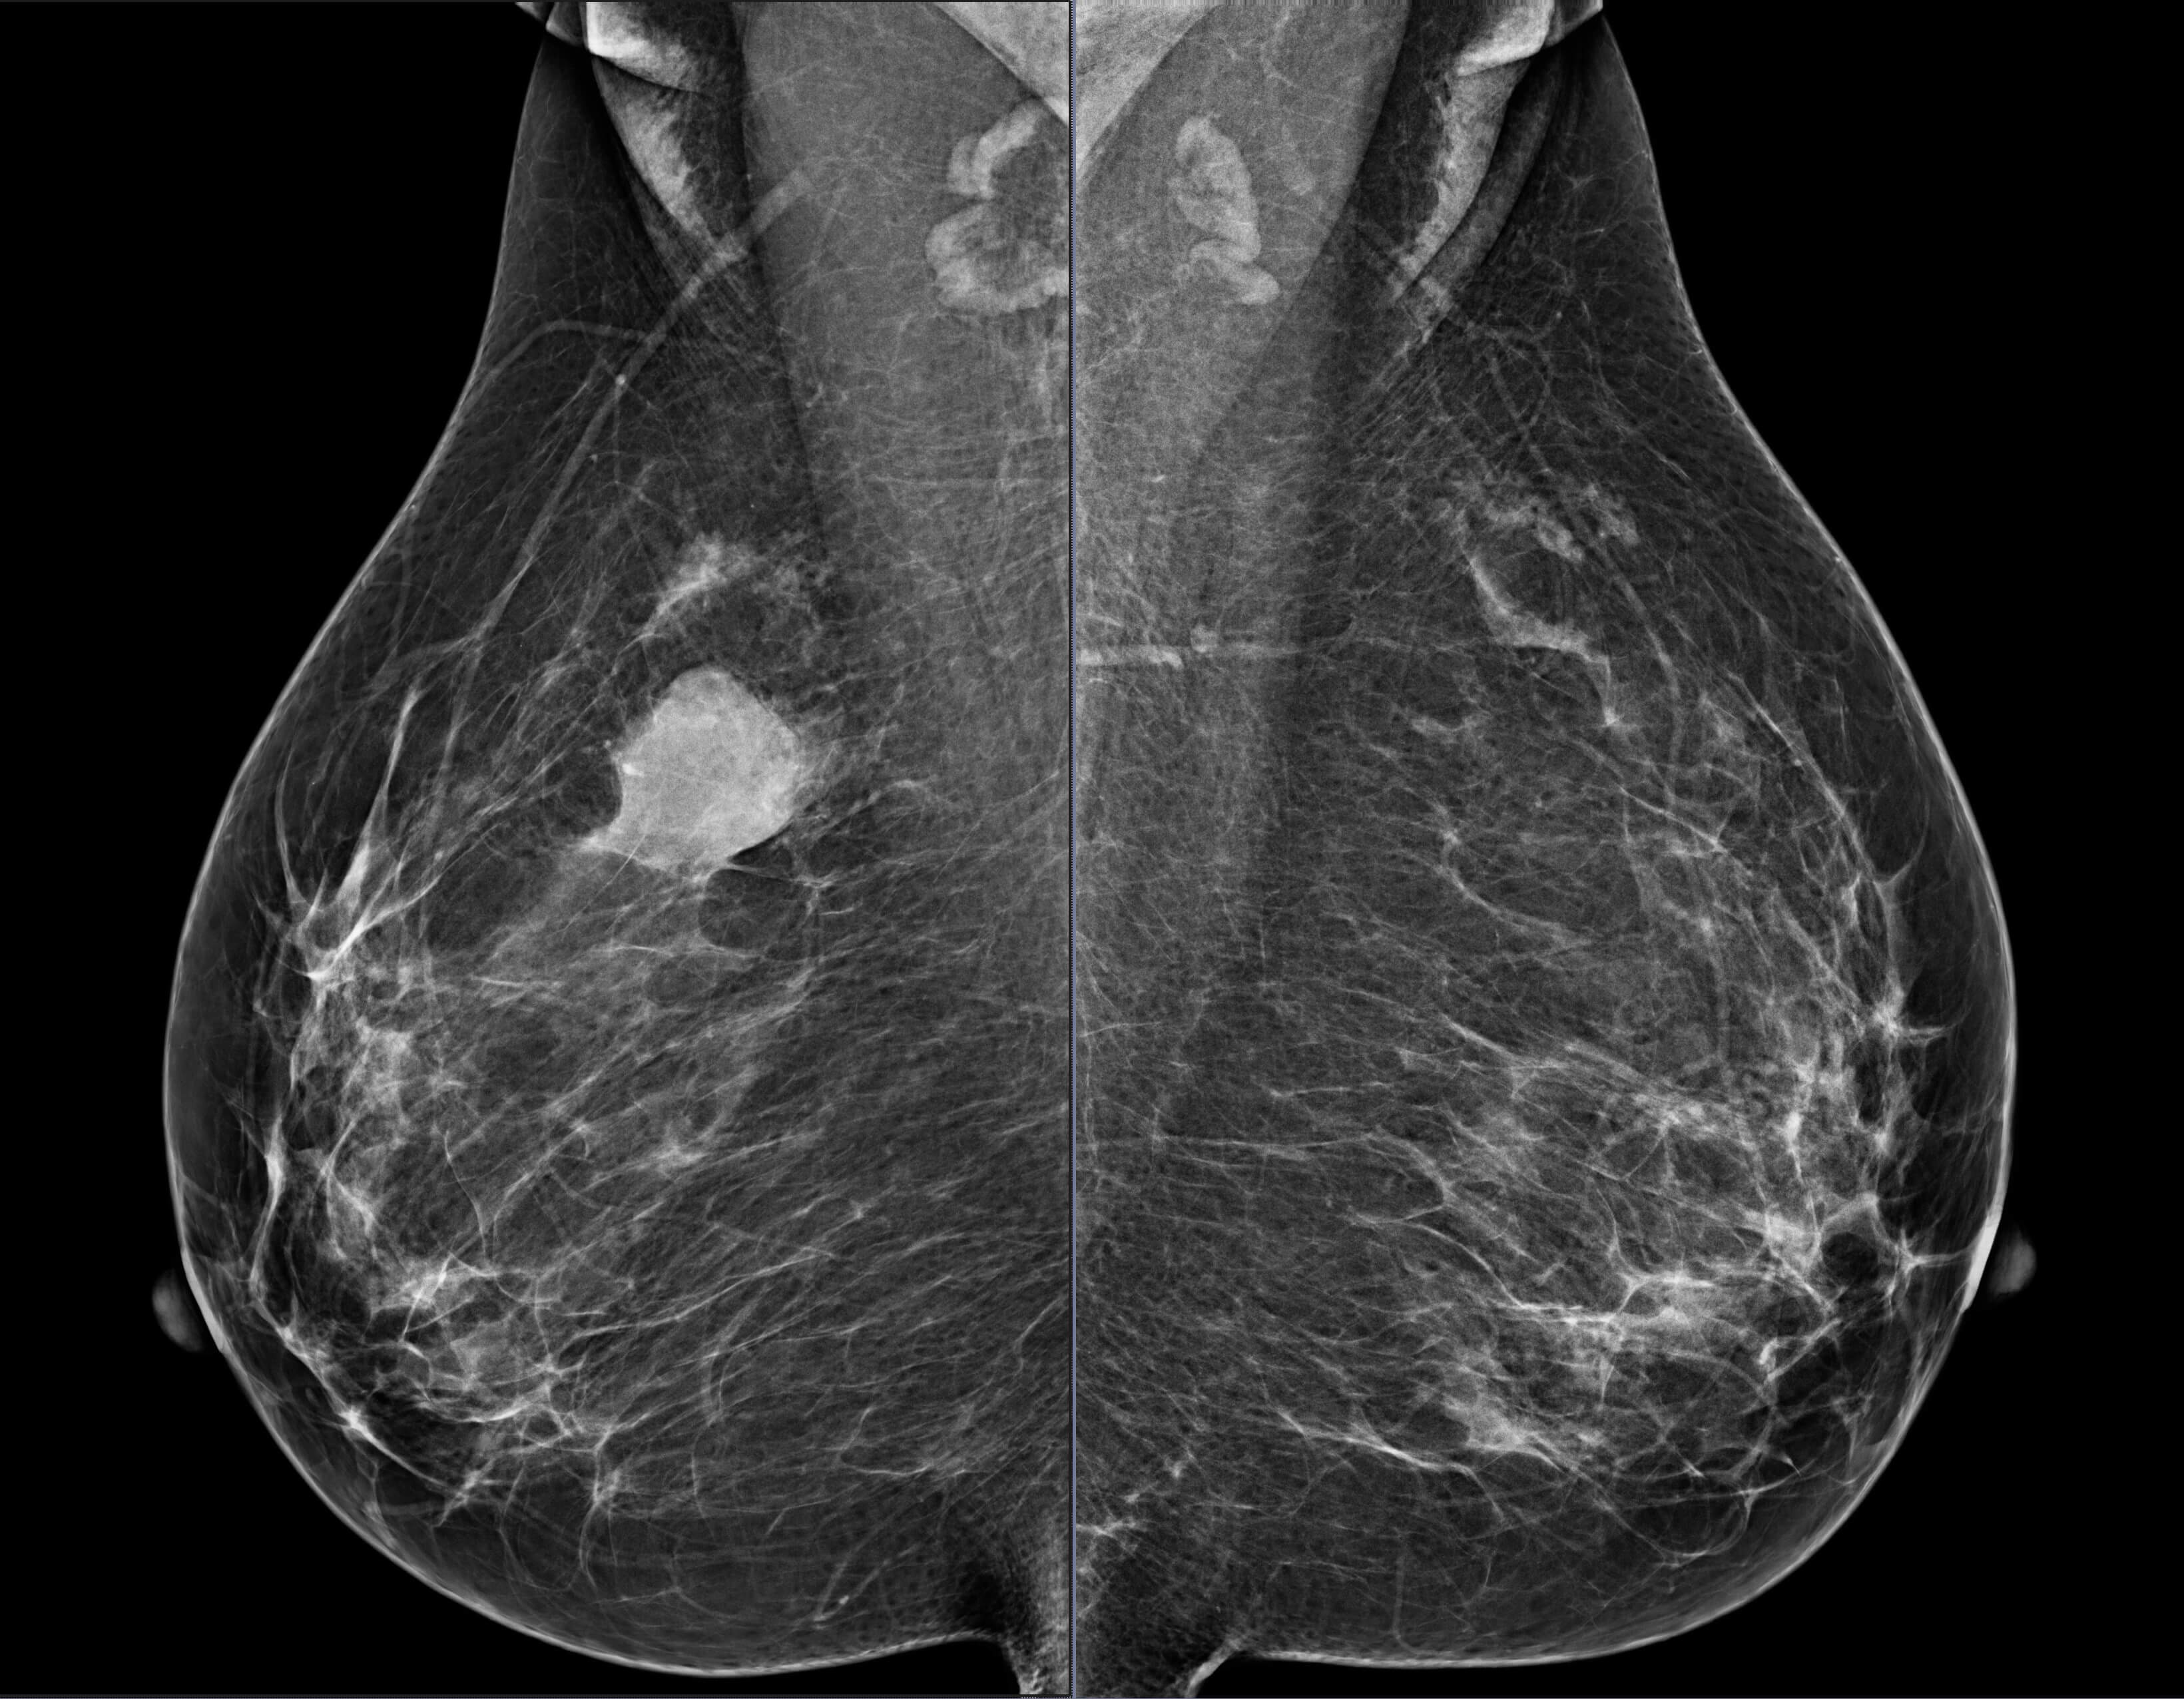

Mammogram revealed the presence of an irregular high density mass in the posterior third of the upper outer quadrant of the right breast with indistinct margins on two-dimensional mammogram. No internal calcification seen. No overlying skin thickening or retraction noted. DBT (Digital breast tomosynthesis) revealed the mass having spiculated margins and irregular shape. Corroborative ultrasound showed an irregular, heteroechoic solid mass at 10-11 O’clock position with anti-parallel orientation, microlobulated margins, posterior enhancement and internal necrotic/ cystic areas within. Mild internal vascularity was seen on color Doppler. No dilated ducts or intraductal extension was seen. No suspicious lymph nodes were present Further recommendation: Ultrasound guided core-needle biopsy with immunohistochemical analysis Management received: Right side lumpectomy with MRM Final histopathology: Metaplastic carcinoma (carcinosarcoma) with no nodal metastasis